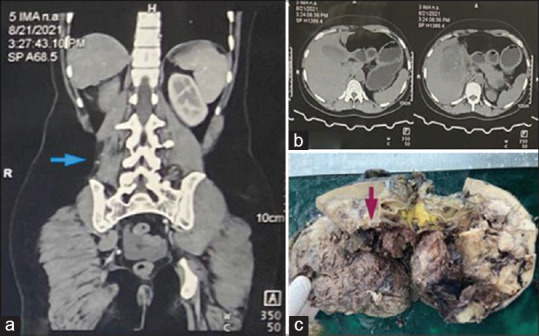

Approximately 5%-10% of soft-tissue tumor comprised synovial sarcoma (SS) and are commonly found in close proximity of large joints affecting young adults. However, SS of the kidney is extremely unusual (1%) and has a poor prognosis. There are three subtypes of primary renal SS (PRSS). The monophasic variant is the most common and shares the same clinical, molecular, and ultrastructural features with other subtypes. Histomorphology with immunohistochemistry (IHC) differentiates it from other sarcomas of kidney and sarcomatoid renal cell carcinoma. Genetic analysis reveals specific SYT-SSX2 (X, 18) translocation. Herein, a case of PRSS (monophasic variant) is presented in a 31-year-old female with right-sided loin pain and huge mass of size (11.9 cm × 9.3 cm × 10 cm) without associated hematuria. It was clinically thought to be renal cell carcinoma. Radical nephrectomy was performed, followed by histopathology and IHC which suggested PRSS. Then, combined chemotherapy of doxorubicin with cyclophosphamide was rendered, and on follow-up, she is doing well with an uneventful course.